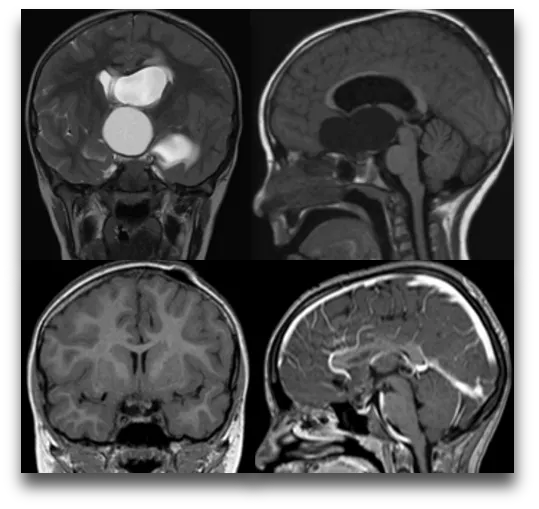

下面这个案例来自鲁特卡教授曾接诊过的一位9岁患儿。她因头痛及视野受限被诊断出一个巨大囊性颅咽管瘤,在经过VP分流术并植入Ommaya储液囊后,肿瘤体积明显缩小,在MRI上几乎看不到。

有没有可以不开颅就切除颅咽管瘤的方法?内镜经鼻手术提供了可能。内镜下经鼻入路切除颅咽管瘤相较于开颅手术有着独特的优势,在提高切除率和视力改善方面也可能优于经颅入路,且不会引起脑牵拉引起的组织损伤。

2023年的一项研究也指出,近年来颅咽管瘤的内镜经鼻入路(EEA)已被证明是广泛切除颅咽管瘤的安全选择,与经颅入路(TCA)相比,这一入路对视神经的损害较小,并且对垂体的可视化效果非常好。EEA有着更高的视力改善率(41.96%vs 25%)及更低的复发率(15.50%vs 21.20%)。说明EEA切除颅咽管瘤与更好的视力保留和肿瘤切除范围相关。